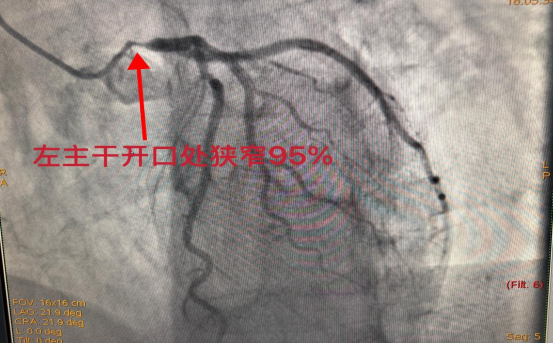

多学科同心护航 90岁骨折老人闯关成功

九旬高龄老人不慎摔倒致肱骨骨折叠加冠脉重度狭窄血糖严重紊乱等...

发布时间:2026-04-13   来源:脊柱创伤外科